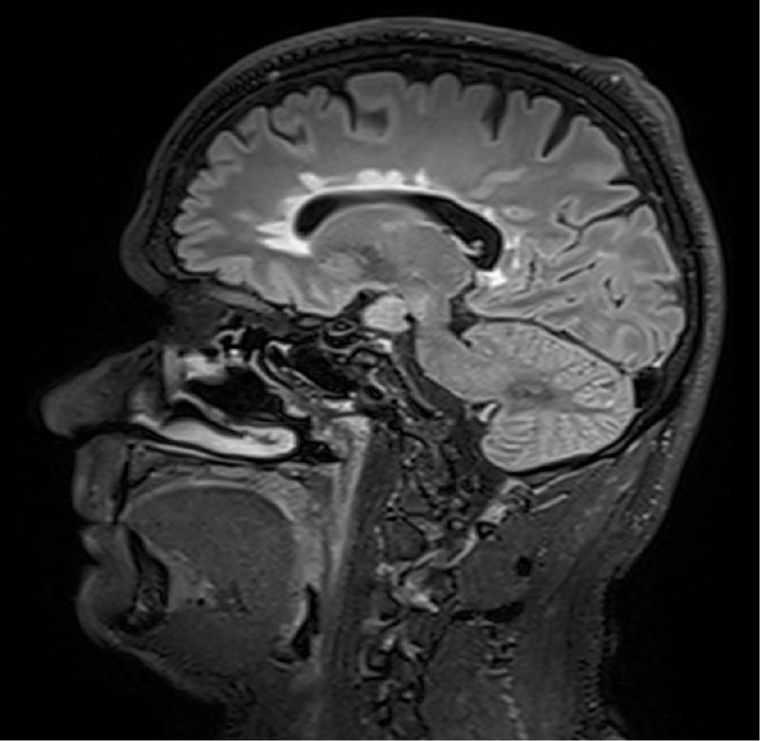

Die Ergebnisse einer neuen Österreichisch-Schweizer Multicenterstudie zu Multipler Sklerose könnten die Therapie dieser chronisch entzündlichen Erkrankung entscheidend verbessern. Forschende der Medizinischen Universitäten Innsbruck und Wien sowie des Inselspitals, Universitätsspital Bern belegen, dass zwei oder mehr in der Magnetresonanztomographie (MRT) sichtbare Läsionen im Gehirn innerhalb eines Jahres für eine Therapieintensivierung sprechen. Damit liegen erstmals eindeutige und evidenzbasierte Kriterien für eine Therapieanpassung vor.

Abseits klinischer Symptome, die von Einschränkungen des Sehvermögens bis hin zu Lähmungserscheinungen ein breites Spektrum umfassen, kann die Krankheitsaktivität bei MS auch bildgebend dargestellt werden. „Der Nachweis entzündlicher Läsionen im Gehirn mittels MRT erlaubt auch eine Einschätzung geringerer Krankheitsaktivität, denn vermeintlich stabile Patienten können trotz Therapie weiterhin neue, klinisch stumme, entzündliche Veränderungen entwickeln“, weiß Neuroimmunologe Harald Hegen, der an der Innsbrucker Universitätsklinik für Neurologie bereits seit vielen Jahren zu MS forscht.

In die Studienkohorte wurden 131 MS-Patienten aus MS-Zentren in Österreich und der Schweiz eingeschlossen, die unter einer gering- bis moderat-effektiven Immuntherapie zwölf Monate lang klinisch stabil waren und dann einer MRT unterzogen wurden. „Wir konnten zeigen, dass Patienten mit schubförmiger MS, die unter Immuntherapie zwei oder mehr neue entzündliche MRT-Läsionen innerhalb eines Jahres entwickeln, auch bei klinischer Stabilität, also ohne Symptome, von einem Wechsel auf eine hoch-effektive Immuntherapie profitieren“, beschreibt Erstautor Gabriel Bsteh von der Medizinischen Universität Wien die zentrale Erkenntnis. Damit liefert die Studie eine für den klinischen Alltag wichtige Erkenntnis, die für die individuelle Therapieanpassung genutzt werden sollte.

„Nachdem Läsionen oft schon vor dem Auftreten klinischer Symptome in der MRT sichtbar sind, ermöglicht eine bildgebende Kontrolle bei Patienten mit einer gering- bis moderat-effektiven Therapie ein frühes Eingreifen in den individuellen Krankheitsverlauf“, betont Studienleiter Harald Hegen. In der Studienkohorte waren rund 40 Prozent der Patienten klinisch stabil, zeigten allerdings in der MRT schon eine oder mehrere Läsionen. Bislang war in der klinischen Praxis eine Therapieverstärkung nur nach Auftreten klinisch manifester Symptome angezeigt.